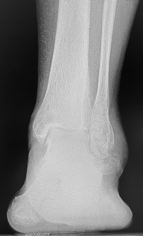

Radiographs showed osseous masses on the lateral aspect of the sinus tarsi and under the fibula with arthrosis of the STJ (Figure 1). The preoperative lateral Meary’s angle was 14º, talar declination angle was 12º, and talocalcaneal angle was 22º. Computed tomography showed arthrosis of the STJ arthrosis involving the posterior facet of the STJ with loss of talar height (Figure 2).